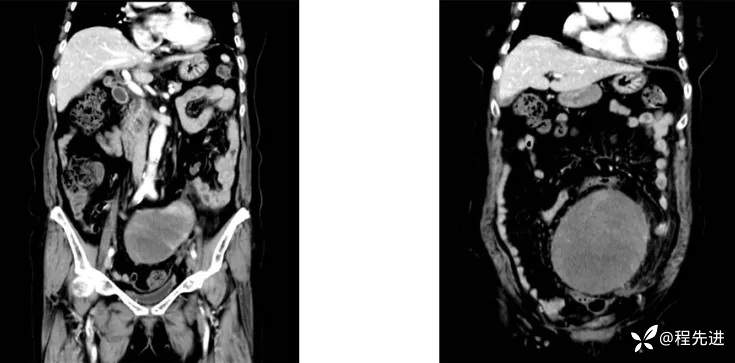

4月后患者再次腹痛半月来诊

CT平扫+增强:

既往史:腹膜后占位性病变切除术后、胆囊结石并慢性胆囊炎、高血压、高脂血症、癫痫。